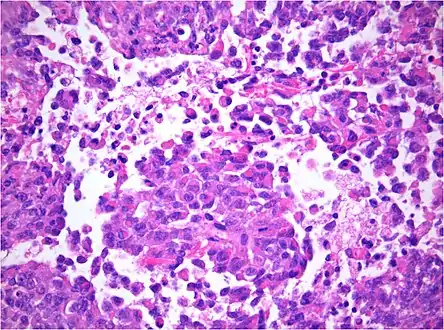

AT/RT and rhabdoid tumor share the term "rhabdoid" because under a microscope, both tumors resemble rhabdomyosarcoma.

AT/RT Histology with numerous rhabdoid tumor cells

AT/RT Histology with numerous rhabdoid tumor cells Rhabdoid Tumor Cell - 400X Magnification

Histology

The tumor histopathology is jumbled small and large cells. The tissue of this tumor contains many different types of cells including the rhabdoid cells, large spindled cells, epithelial and mesenchymal cells, and areas resembling primitive neuroectodermal tumor (PNET). As much as 70% of the tumor may be made up of PNET-like cells. Ultrastructure characteristic whorls of intermediate filaments are seen in the rhabdoid tumors (as with rhabdoid tumors in any area of the body). Ho and associates found sickle-shaped embracing cells, previously unreported, in all of 11 cases of AT/RT.[18]